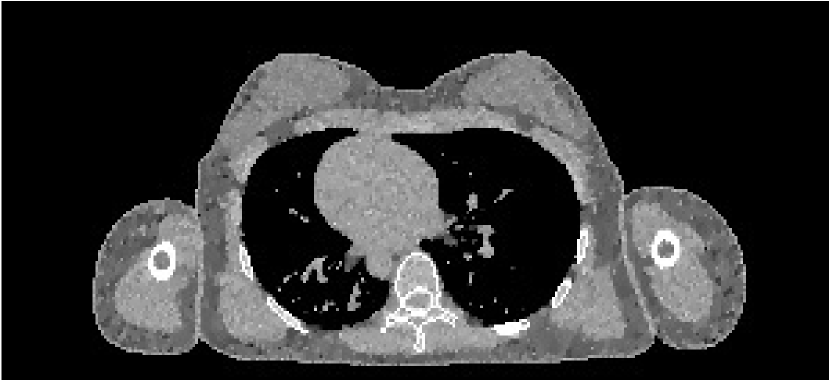

The results from our reconstruction test are illustrated in Figure 9 and Table 3.

Refer to caption

(a) FBP chest

(b) FBP pelvis

(c) PWLS chest

(d) PWLS pelvis

(e) Poly-SIR chest

(f) Poly-SIR pelvis

(g) IMPACT chest

(h) IMPACT pelvis

(i) Polyquant chest

(j) Polyquant pelvis

Figure 9: Results from electron density reconstruction test for chest and pelvis fan-beam data with display window [0.8,1.2] to aid visualisation of soft tissue and reconstruction artefacts

chest datapelvis dataSchemeρe RMSEρ RMSEρe RMSEρ RMSEFBP0.1360.1400.2010.226PWLS0.03890.04260.1330.166Poly-SIR0.03630.03850.08390.101IMPACT0.03070.03260.1330.159Polyquant0.02980.03160.05130.0746missing-subexpressionmissing-subexpressionmissing-subexpressionmissing-subexpressionmissing-subexpressionmissing-subexpressionchest datapelvis datamissing-subexpressionmissing-subexpressionmissing-subexpressionmissing-subexpressionmissing-subexpressionSchemesubscript𝜌𝑒 RMSE𝜌 RMSEsubscript𝜌𝑒 RMSE𝜌 RMSEmissing-subexpressionmissing-subexpressionmissing-subexpressionmissing-subexpressionmissing-subexpressionFBP0.1360.1400.2010.226PWLS0.03890.04260.1330.166Poly-SIR0.03630.03850.08390.101IMPACT0.03070.03260.1330.159Polyquant0.02980.03160.05130.0746\begin{array}[]{c|c|c|c|c|}\cline{2-5}\cr&\lx@intercol\hfil\text{chest data}\hfil\lx@intercol&\vrule\lx@intercol\hfil\text{pelvis data}\hfil\lx@intercol\vrule\lx@intercol\\ \cline{2-5}\cr\text{Scheme}&\rho_{e}\text{ RMSE}&\rho\text{ RMSE}&\rho_{e}\text{ RMSE}&\rho\text{ RMSE}\\ \hline\cr\text{FBP}&0.136&0.140&0.201&0.226\\ \text{PWLS}&0.0389&0.0426&0.133&0.166\\ \text{Poly-SIR}&0.0363&0.0385&0.0839&0.101\\ \text{IMPACT}&0.0307&0.0326&0.133&0.159\\ \text{Polyquant}&\mathbf{0.0298}&\mathbf{0.0316}&\mathbf{0.0513}&\mathbf{0.0746}\\ \hline\cr\end{array}

In terms of both electron density and mass density accuracy, our proposed method is the best performing method under test. The lack in estimation accuracy in using the water–bone model with Poly-SIR is likely to be due to discrepancies in adipose and spongy bone tissues from water, which were illustrated in Figure 5. We note that Poly-SIR is second best performing in the pelvis case, but it was provided with oracle information on the implant and hard bone, which would be difficult to segment in practice from a preliminary reconstruction such as FBP due to its high noise. IMPACT is understandably very closely performing to our method in the chest case, as these performed similarly in the model test, but the advantage of fitting at each energy is clear in the case of the metal implant, where the IMPACT performance is similar to that of PWLS.